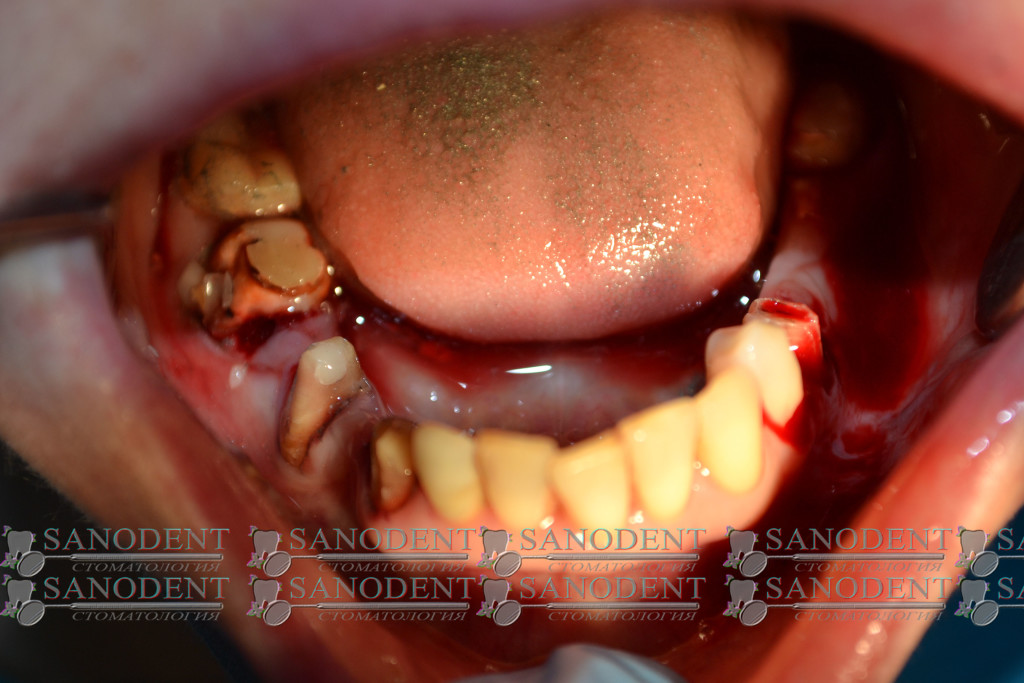

Протезирование безметалловыми прессованными керамическими коронками E-max, с опорой на немецких имплантаx ICX и циркониевых абатментах:

- Вид до лечения:

- Начинаем снимать старые мосты

- Снимаем старые мосты низ:

- убрали все «мертвое»:

- начинаем установку имплантов:

- имплантация зубов: